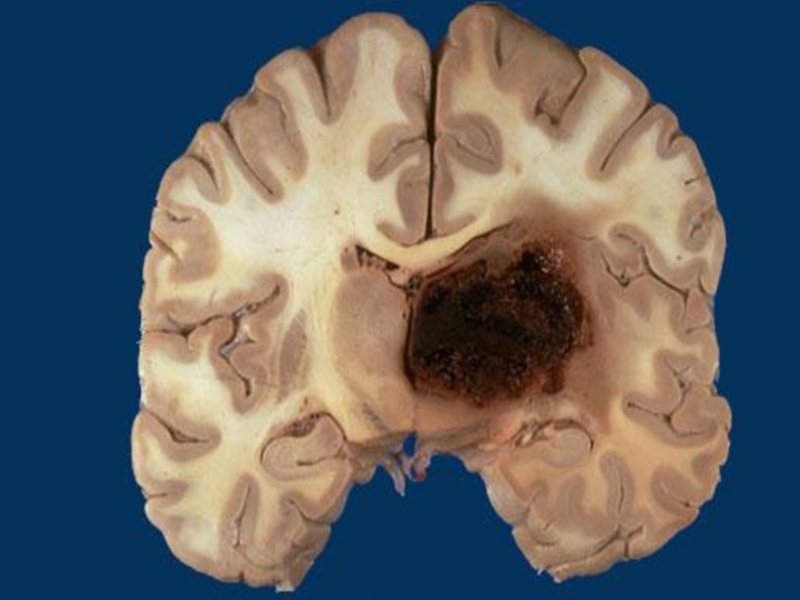

Слайд 64Types of cerebral hemorrhages:

Without the structure destruction – diapedetic

With the

structure destruction – hematomas

Especially dangerous – hemorrhages in basal ganglia

of brain, brainstem, break into ventricles of brain

Types of cerebral hemorrhages: Without the structure destruction – diapedeticWith the structure destruction – hematomasEspecially dangerous –